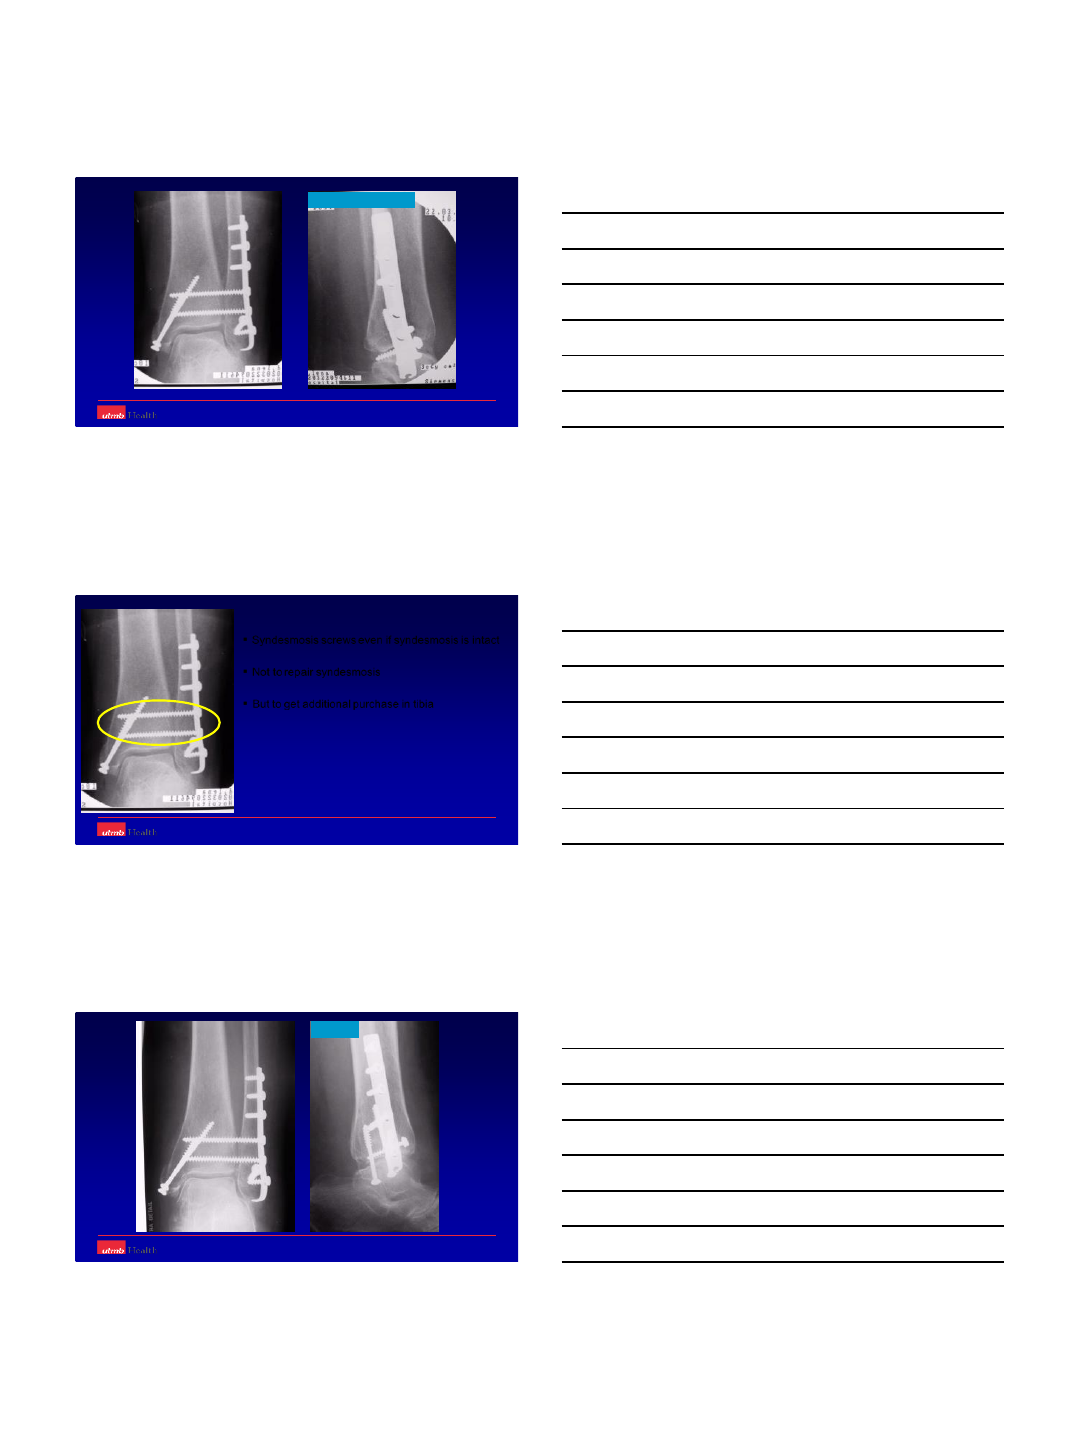

ORIF –standard fixation

What should we do different ??

–can fail

Augmented ORIF

Hook Plate and Tibia-Pro-Fibula Screws

80 Yr F - Fit and active

20

‘Wrinkle ready’ for ORIF at 2 wks.

21

The ‘wrong’ bend

The

‘Right’

Curves

21-11-02

76 yrs. F16-03-02

22

22-03-02 Intraoperative images

22-03-02

Syndesmosis screws even if syndesmosis is intact

Not to repair syndesmosis

But to get additional purchase in tibia

3 months

11-06-03